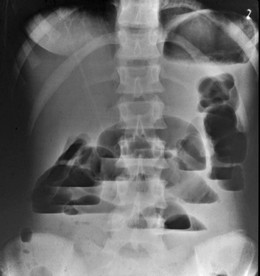

Всички болни, при които има съмнение за чревна непроходимост трябва да бъдат консултирани с хирург. Уточняването на диагнозата става след подробен преглед на болния и задължително рентгеново изследване на корема.

Според мястото на чревната непроходимост – в тънкото или дебелото черво има известни разлики в началото и протичането на заболяването.

Тънкочревен илеус

Началото на тънкочревната чревна непроходимост обикновено е бурно, със силни коремни болки, локализирани около пъпа. Болките са коликообразни, с периоди на засилване и отслабване, придружени с упорито повръщане отначало на стомашно, а след това на чревно съдържимо (мiserere). Умереният метеоризъм (подуване на корема) е постоянен симптом на заболяването.

Дебелочревен илеус

Началото на заболяването при дебелочревна непроходимост, особено при туморни заболявания е постепенно, с напредващо подуване на корема, понякога до големи размери, спира отделянето на газове и изпражнения, слаби до умерени болки в епи- или хипогастриума, по-късно започва повръщане на чревно съдържимо. При заклещване на херния или усукване на чревна бримка заболяването протича по-бурно.